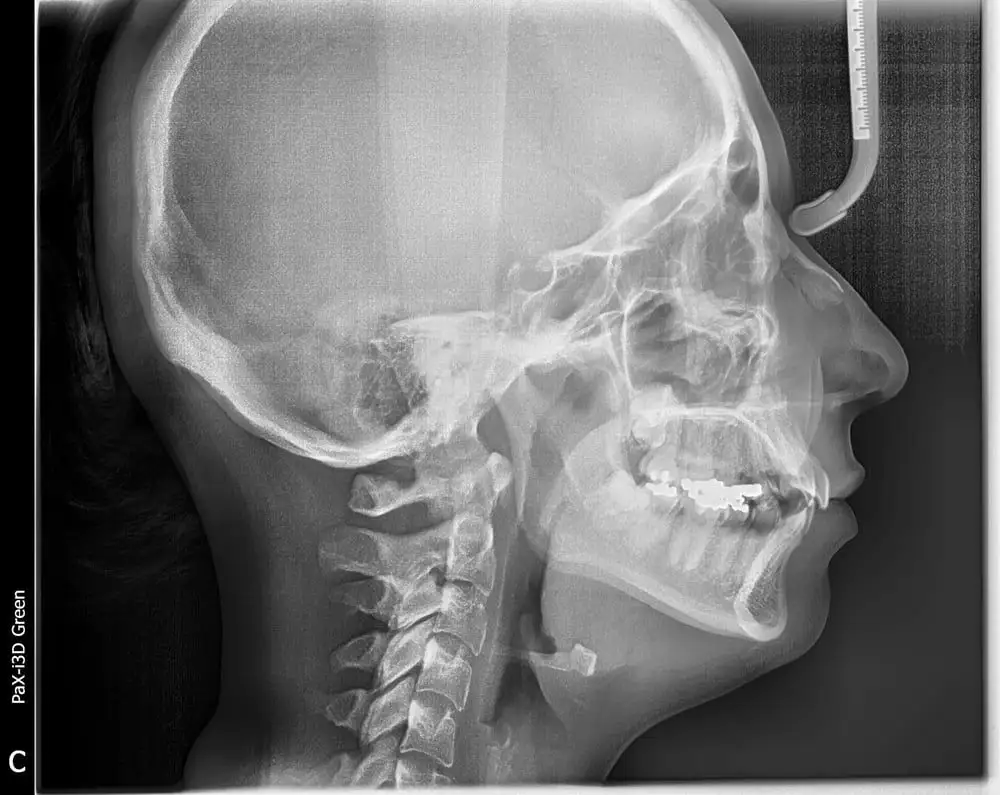

The Panorex is also capable of taking cephalometric images which gives us a lateral view of the skull and its facial structures. This is very useful in orthopedic correction of boney structures during orthodontics and TMJ treatment.